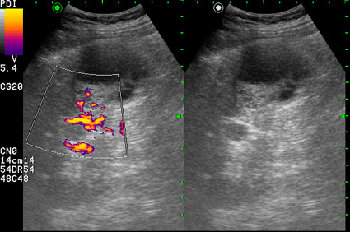

Сонограмма правой почки у женщины 42 лет. Женщина болеет сахарным диабетом, профилактический осмотр.

Как трактовать выявленные изменения? Какова тактика врача УЗД в данной ситуации?

по Bosniak-type3-indetrminate lezion- показана биопсия

Почечно-клеточный рак, тип "опухоль в кисте" ?

RCC. Тип "опухоль в кисте".